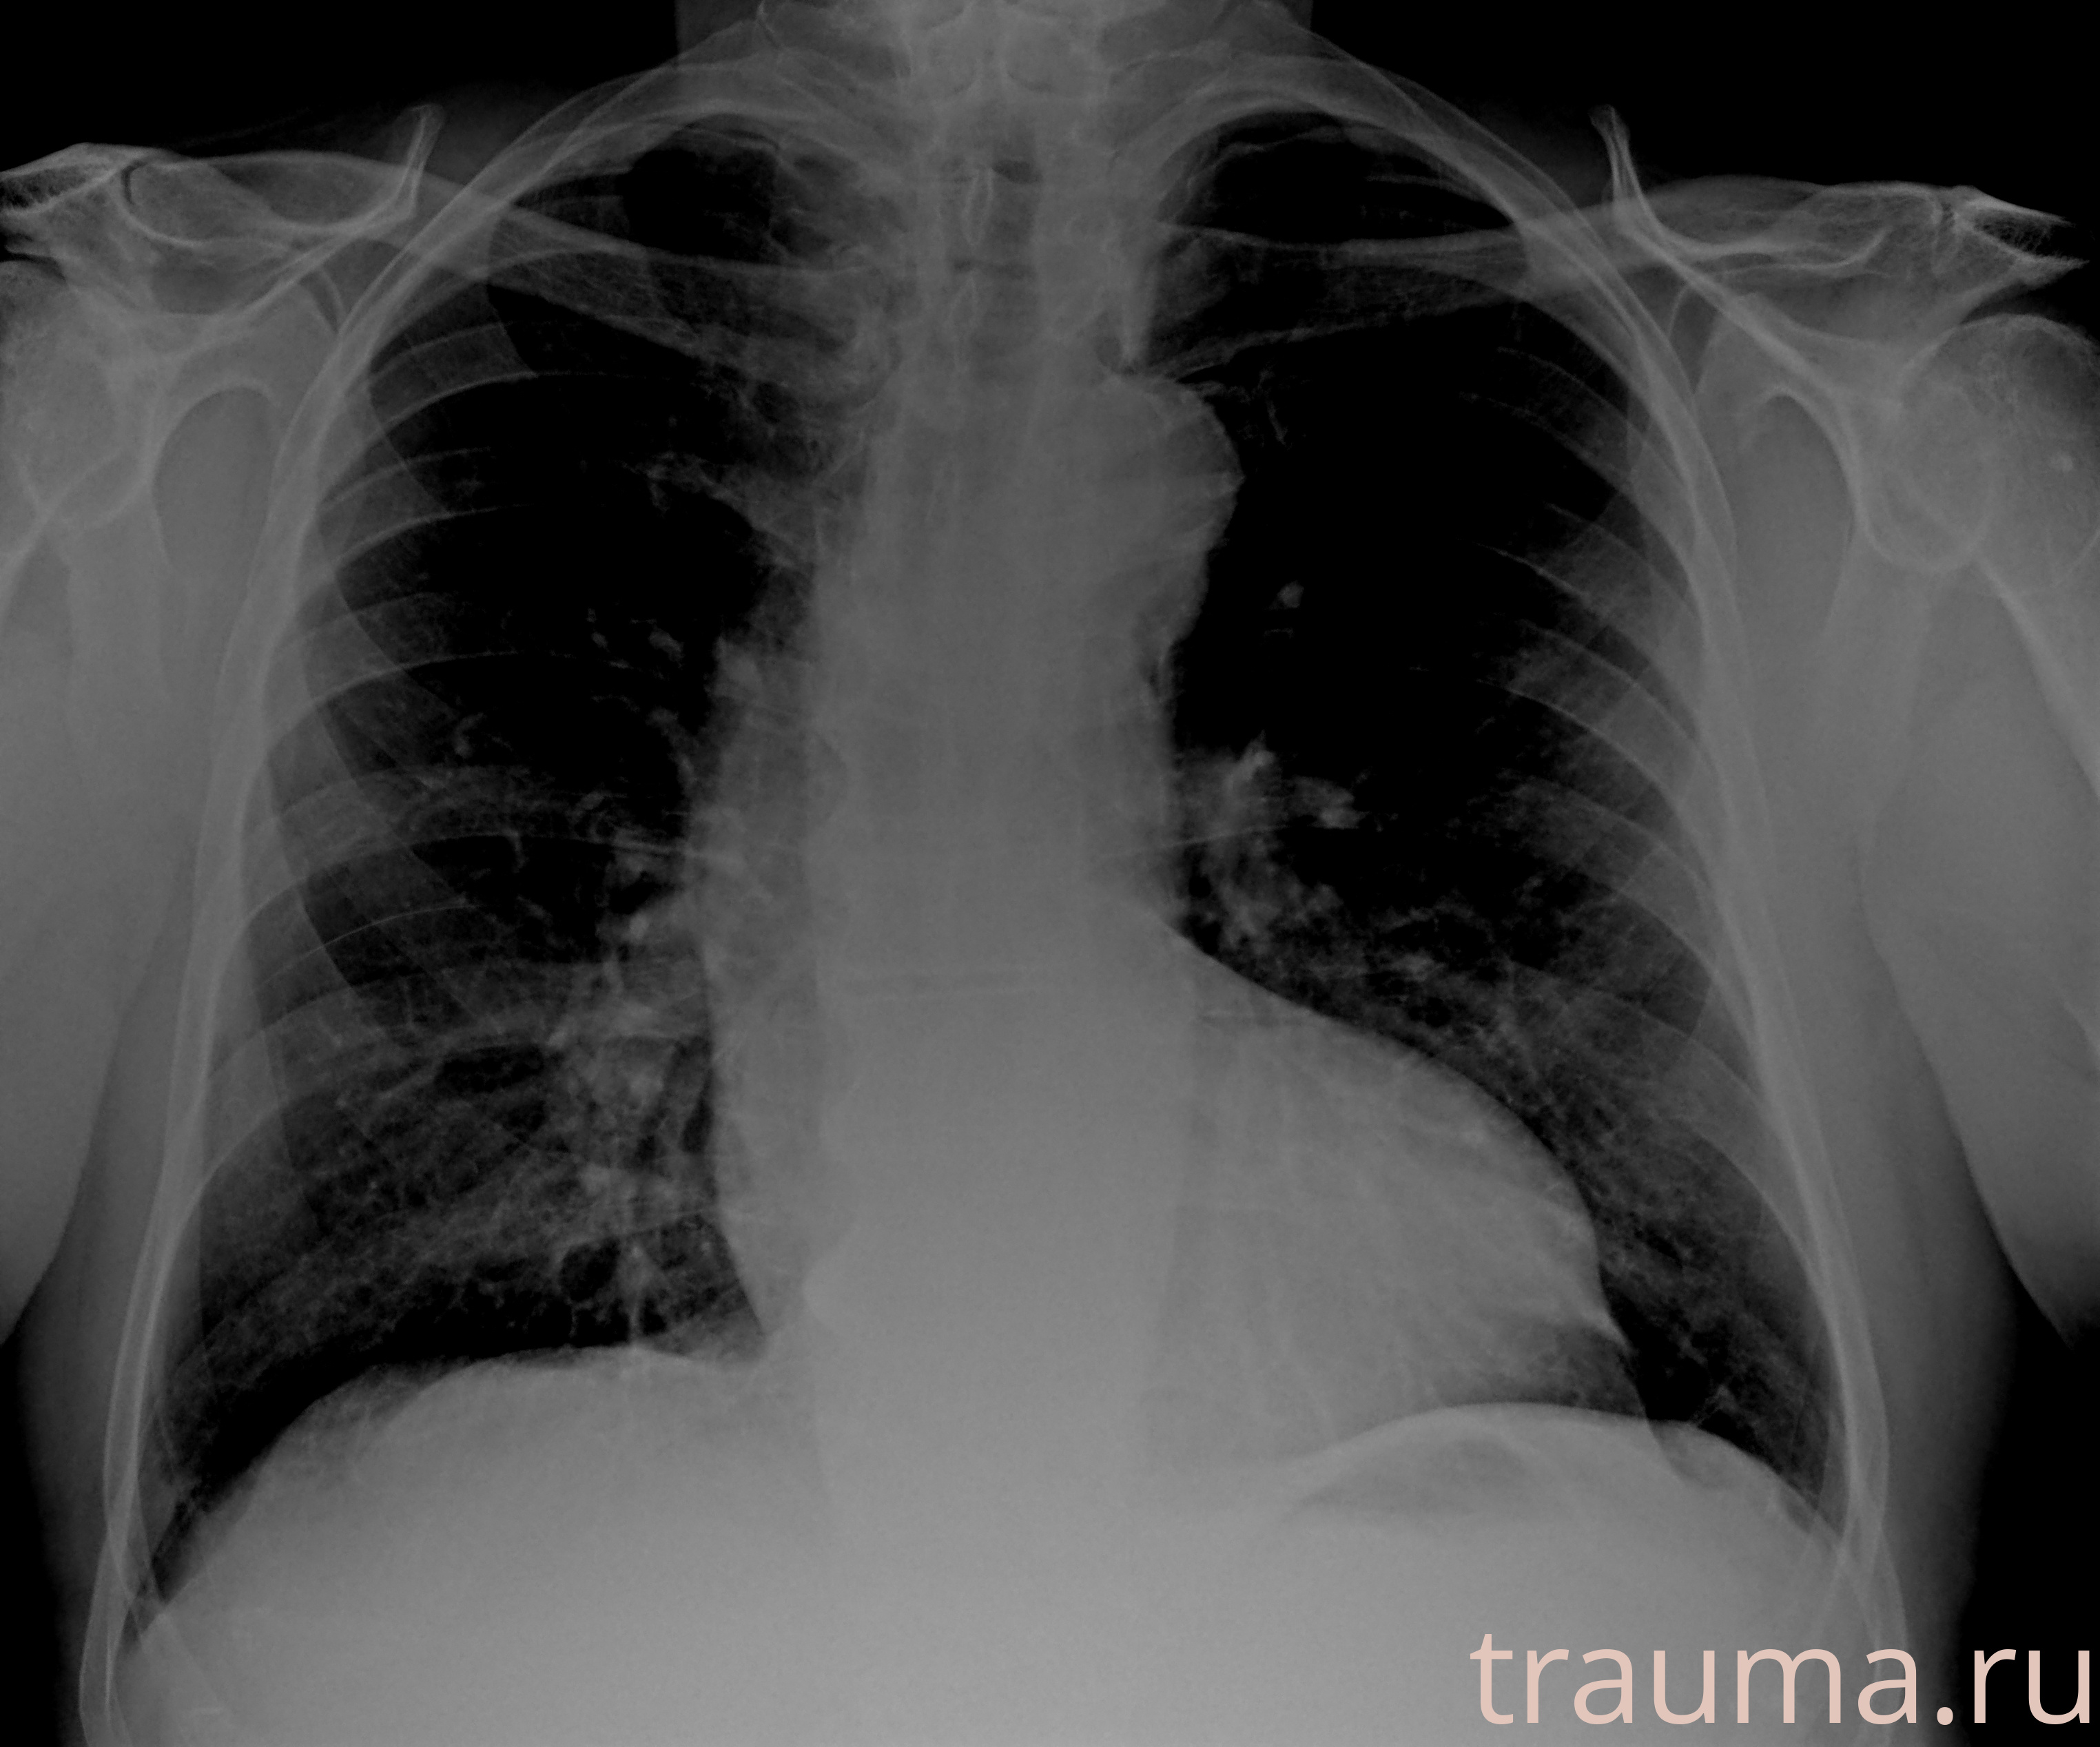

Рентгенограммы

Рентген на дому: по вашему адресу приезжает врач-рентгенолог, травматолог-ортопед с мобильным рентгеновским аппаратом, проводит диагностику травмы или заболевания, делает необходимые рентгенограммы, дает рекомендации по дальнейшему лечению. Получить качественные снимки в домашних условиях возможно благодаря уникальной методике, разработанной МосРентген Центром для института  Склифосовского

Яркость: 1   Контраст: 1   Инвертировать: 0 Увеличение: 1

Перетаскивайте мышь вверх/вниз для контраста, влево/право для яркости. Прокрутка колесом изменяет масштаб. Нажмите Сбросить для возврата к исходному изображению. При увеличении держите мышь в той области, которую хотите рассмотреть.